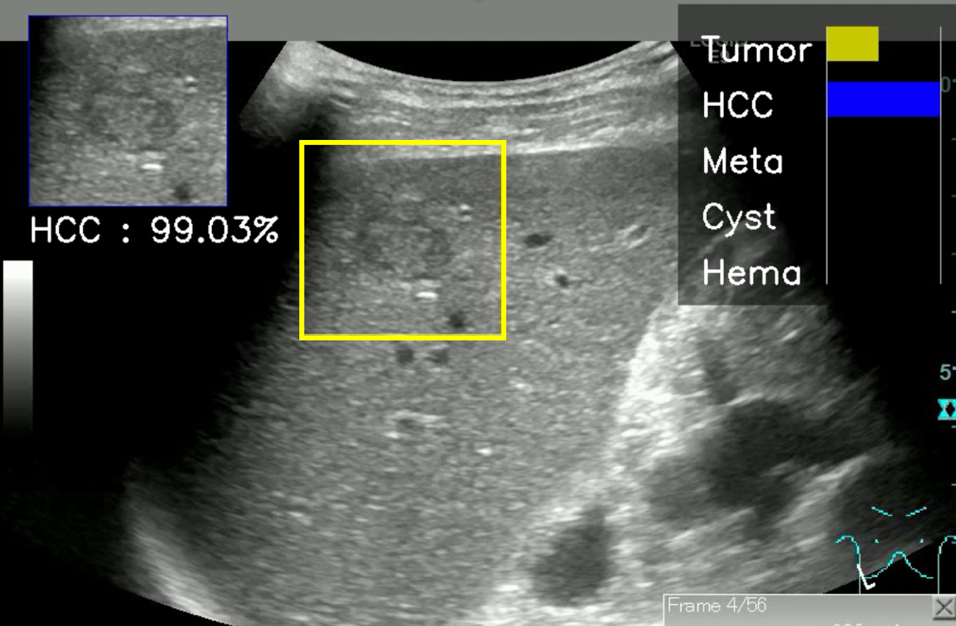

フィリップス、「Liver Fat Quantification(肝脂肪化定量評価。肝臓がん|消化器|診療内容|医療法人 甘木第一クリニック。肝臓がん|消化器|診療内容|医療法人 甘木第一クリニック。sakuraさん専用 蔵王吊るし柿4kg 紅干し柿 600g。Contrast Enhanced Ultrasound (CEUS) | フィリップスヘルスケア。Liver Ultrasonography | SpringerLink。キヤノンメディカルシステムズ、『肝臓の脂肪量の汎用超音波画像。Imaging Features of Hepatocellular Carcinoma in the Non。Imaging Features of Hepatocellular Carcinoma in the Non。714cFtk9QyL._AC_UF350,。肝臓病変における超音波の最新情報-第24回腹部放射線研究会。KMS_M01_XXX_670.jpg。腹部の超音波検査健康なヒト胆嚢 - 胆嚢のストックフォトや画像。